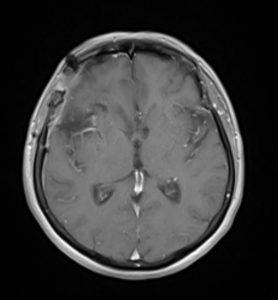

Η μετεγχειρητική αξονική τομογραφία εγκεφάλου δείχνει αφαίρεση της βλάβης χωρίς παρουσία επιπλοκών, και κυρίως χωρίς κάποιο έμφρακτο από τα εμπλεκόμενα αγγεία. Η ιστολογική εξέταση ανέδειξε μηνιγγίωμα, WHO Grade I.

Μετεγχειρητικά η ασθενής ήταν άριστη νευρολογικά και εξήλθε του νοσοκομείου την 4η μετεγχειρητική ημέρα.